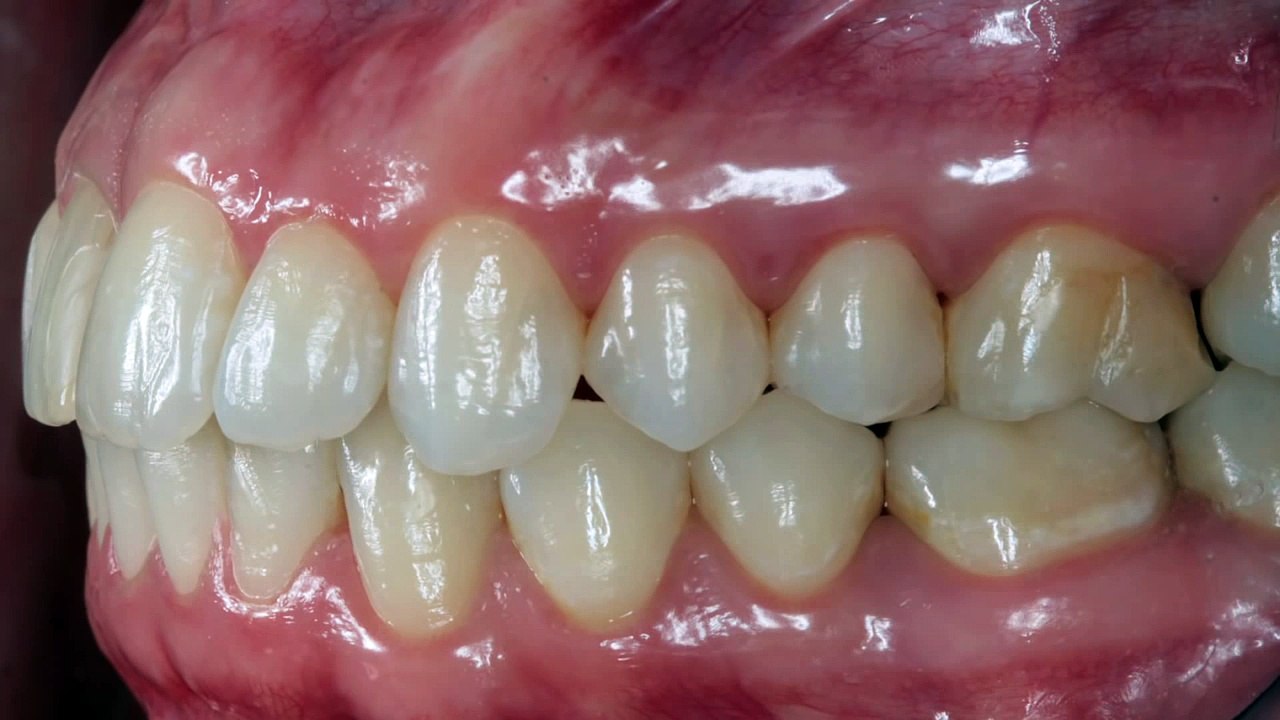

In case of tooth pain you'll be able to contact the appropriate tooth doctor associated 1st they're going to recommend you for an x-ray from that the problems may be determined. however you've got to pick out the correct tooth doctor and understand the treatments they supply. The dental digital x rays provide the foremost distinctive approach of scratching over the pc screen then on. <br /><br />Visit @ http://sotaimaging.net